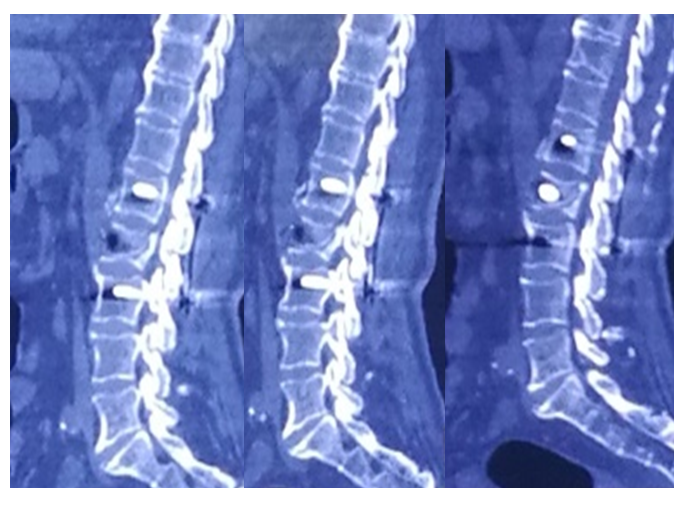

术前CT

术后CT

•      术后3月CT